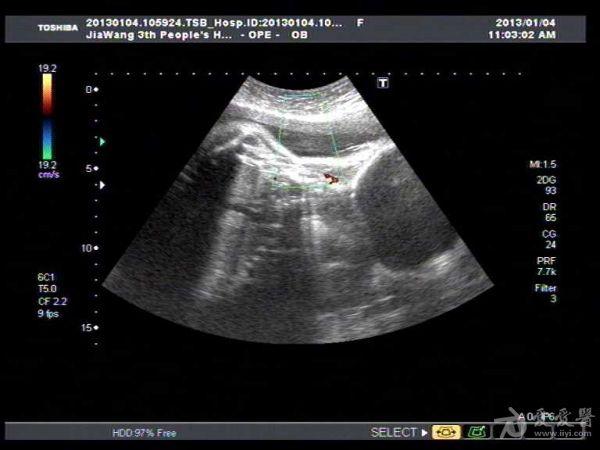

此孕妇听信家人说吃核桃能补脑,吃了两个月核桃来来复查,脑积水更明显。